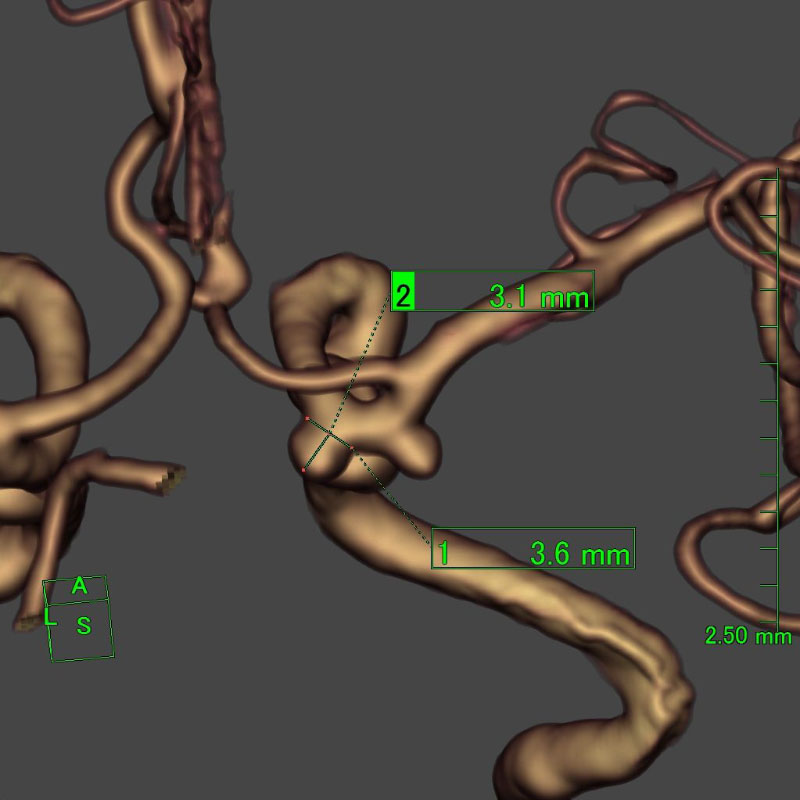

※ 画像をクリックすると拡大表示します。症例No.をクリックすると詳細ページを表示します。

手術前

クリップ前

クリップ後

手術後